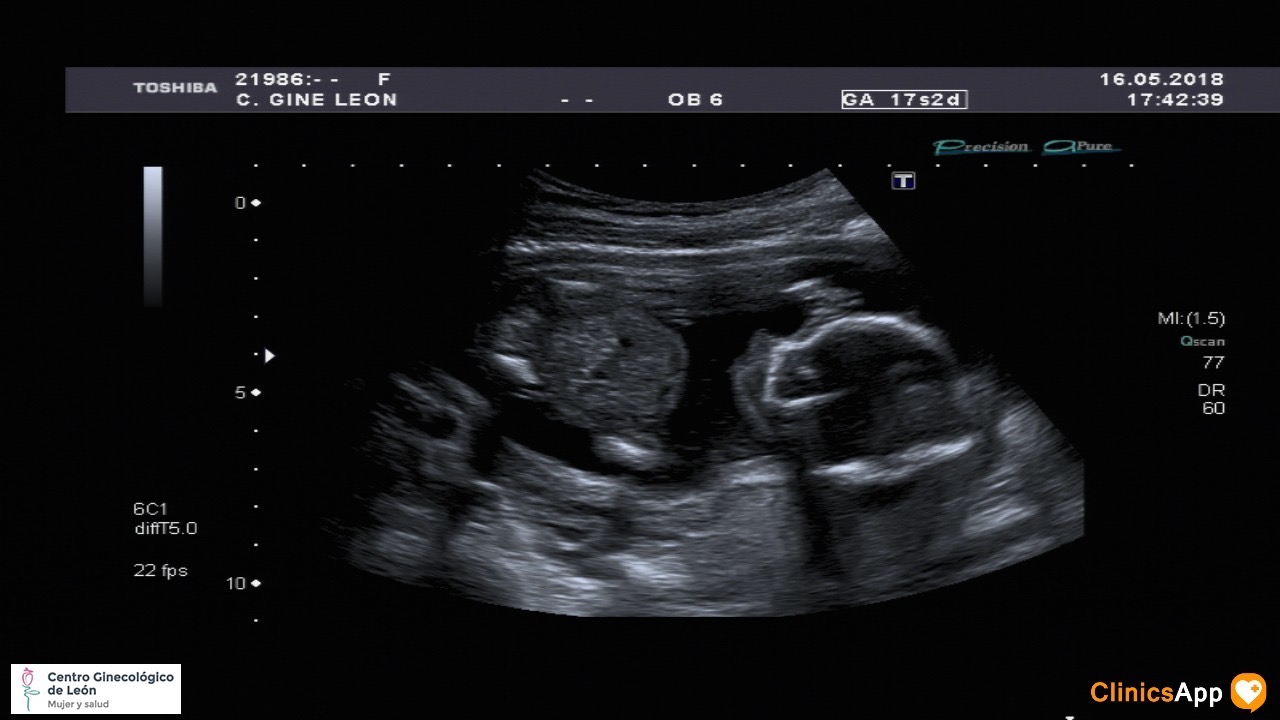

Pues sí, parece que para finales de octubre Mateo tendrá una hermana. Se aceptan sugerencias de nombres de niña, porque no lo tenemos muy claro y me temo que va a ser un asunto complicado. Ayer Mateo estaba un poco nervioso antes de entrar, no sabemos si lo ha asimilado todavía.

Ecografías de hoy